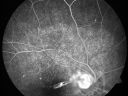

Toxocariasis770 views15-year-old one year ago had pink eye then her vision has been abnormal. She recently went for a drivers’ test and failed, OD: 20/80; OS: 20/20.